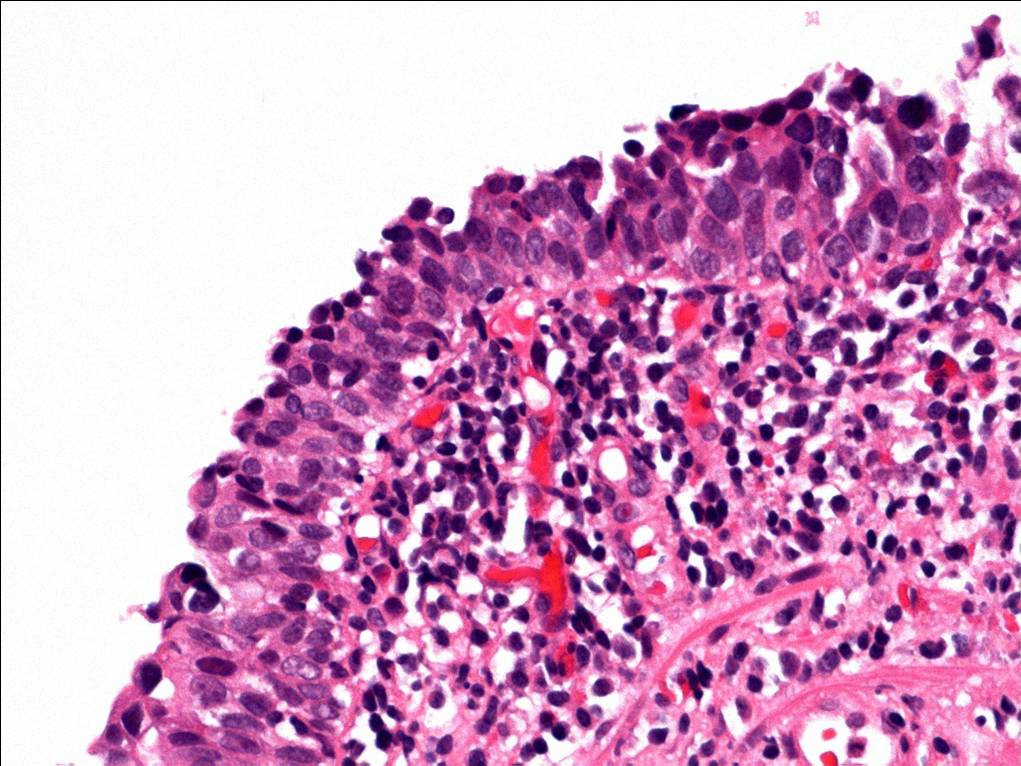

Consensus grade: Carcinoma in situ (CIS)

Case description (by case creator):

The degree of cytologic atypia and loss of polarity is disproportionate to the inflammation present in the lamina propria and the degree of atypia is greater than would be acceptable for reactive atypia.